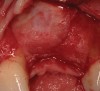

A 46-year-old patient presented with a long-standing fixed partial denture replacing tooth No. 9 (Figure 24). The distal abutment No. 10 was fractured, and the patient was referred for implant reconstruction. During the consultation, the patient expressed a desire to have individual teeth back. Both the periodontist and the restorative dentist recommended a single fixture No. 9 with a cantilevered No. 10 pontic. Due to the bone loss present on the mesial aspect of tooth No. 9 and the bone loss present on the mesial aspect of tooth No. 10, this solution was felt to be the most predictable, using augmentation to build a pontic site for No. 10. Despite extensive consultation, due to the patient’s insistence on single teeth, expectations for an ideal result needed to be managed and the patient accepted therapy understanding that esthetics would most likely be compromised with little chance of complete regeneration (Figure 25 through Figure 33).